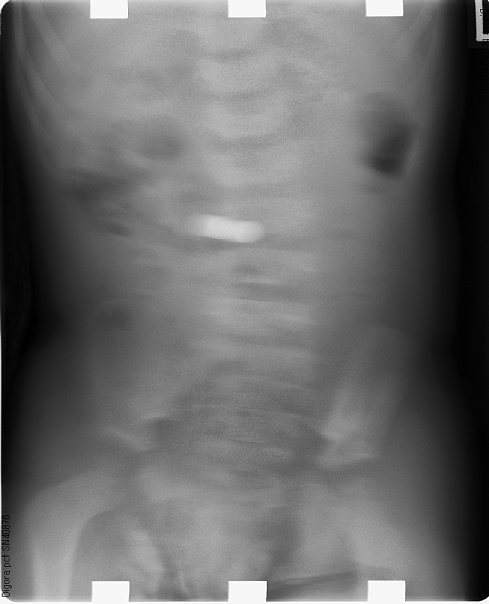

夜中ではありましたが、病院の救急外来に急遽受診。そちらでも改めてレントゲンを撮った所、やはりくっきりと電池の陰が確認されました。